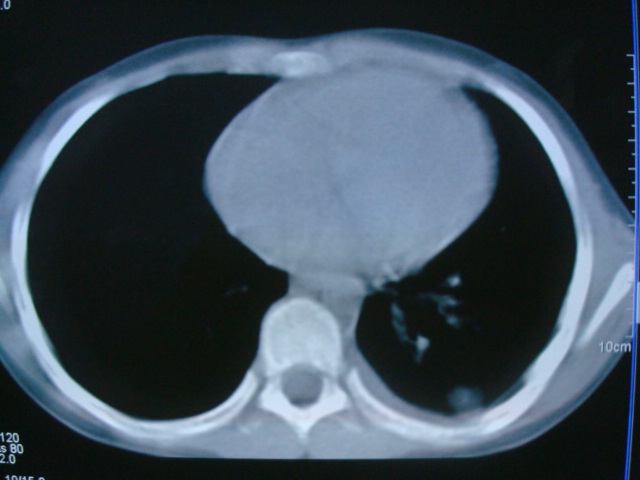

标题: PED0869:男,10岁,肺内多发结节+胸水 [打印本页]

标题: PED0869:男,10岁,肺内多发结节+胸水

男,10岁,左胸痛,发热轻,血象高。后到省级权威医院治疗,病情明显好转,结果几天后公布。老机器,图像质量差,见谅。

考虑血源性肺脓肿或韦氏肉芽肿

血源性肺脓肿可能。

考虑血源性肺脓肿.支持!